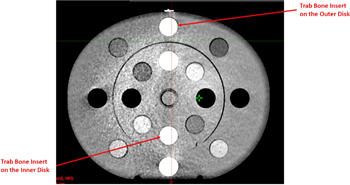

For 100 kV, not only was the HU deviation between the reference scan and other scans substantial, but the standard deviation of most scatter conditions was out of tolerance, rendering them unsuitable for dose calculations. This is because the 100 kV Head protocol is designed specifically for the H&N configuration, the typical width and length of which is approximately 15 cm and 18 cm, respectively. Therefore, when only the inner disk of the CIRS CTED phantom was scanned, both the reproducibility and the SNR of the scan were acceptable. In contrast, for the other scans where the geometry of the scanned material was larger, both the HU difference and the standard deviation were out of tolerance (i.e., >50 HU in the adipose—liver range or >100 HU in other materials). An example of Scan 4 acquired with the 100 kV Head protocol on HAL1 is shown in figure 5, which illustrates both the HU deviation between the inner and the outer disks as well as the increased noise.

Figure 5. CBCT image of the CIRS CTED phantom acquired with the 100 kV Head protocol. Obvious noise and artefacts were observed. The two trabecular bone (Trab Bone) inserts, which had the same density, are highlighted.

Standard image High-resolution imageHU response results for the 125 kV and 140 kV protocols were similar across the scan variants. Table 5 shows that the standard deviations of both tube voltages were within the tolerance across the two linacs, indicating that the SNRs of both protocols were acceptable. This can also be seen from figure 6, which, compared to figure 5, shows significantly higher SNR under the same scatter condition.

Figure 6. CBCT image of the CIRS CTED phantom acquired with the 125 kV Pelvis protocol.